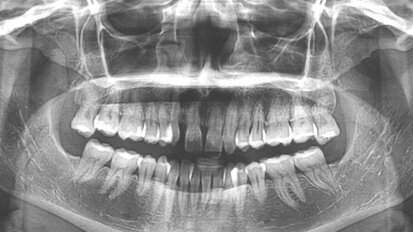

Hybridní terapie alignery